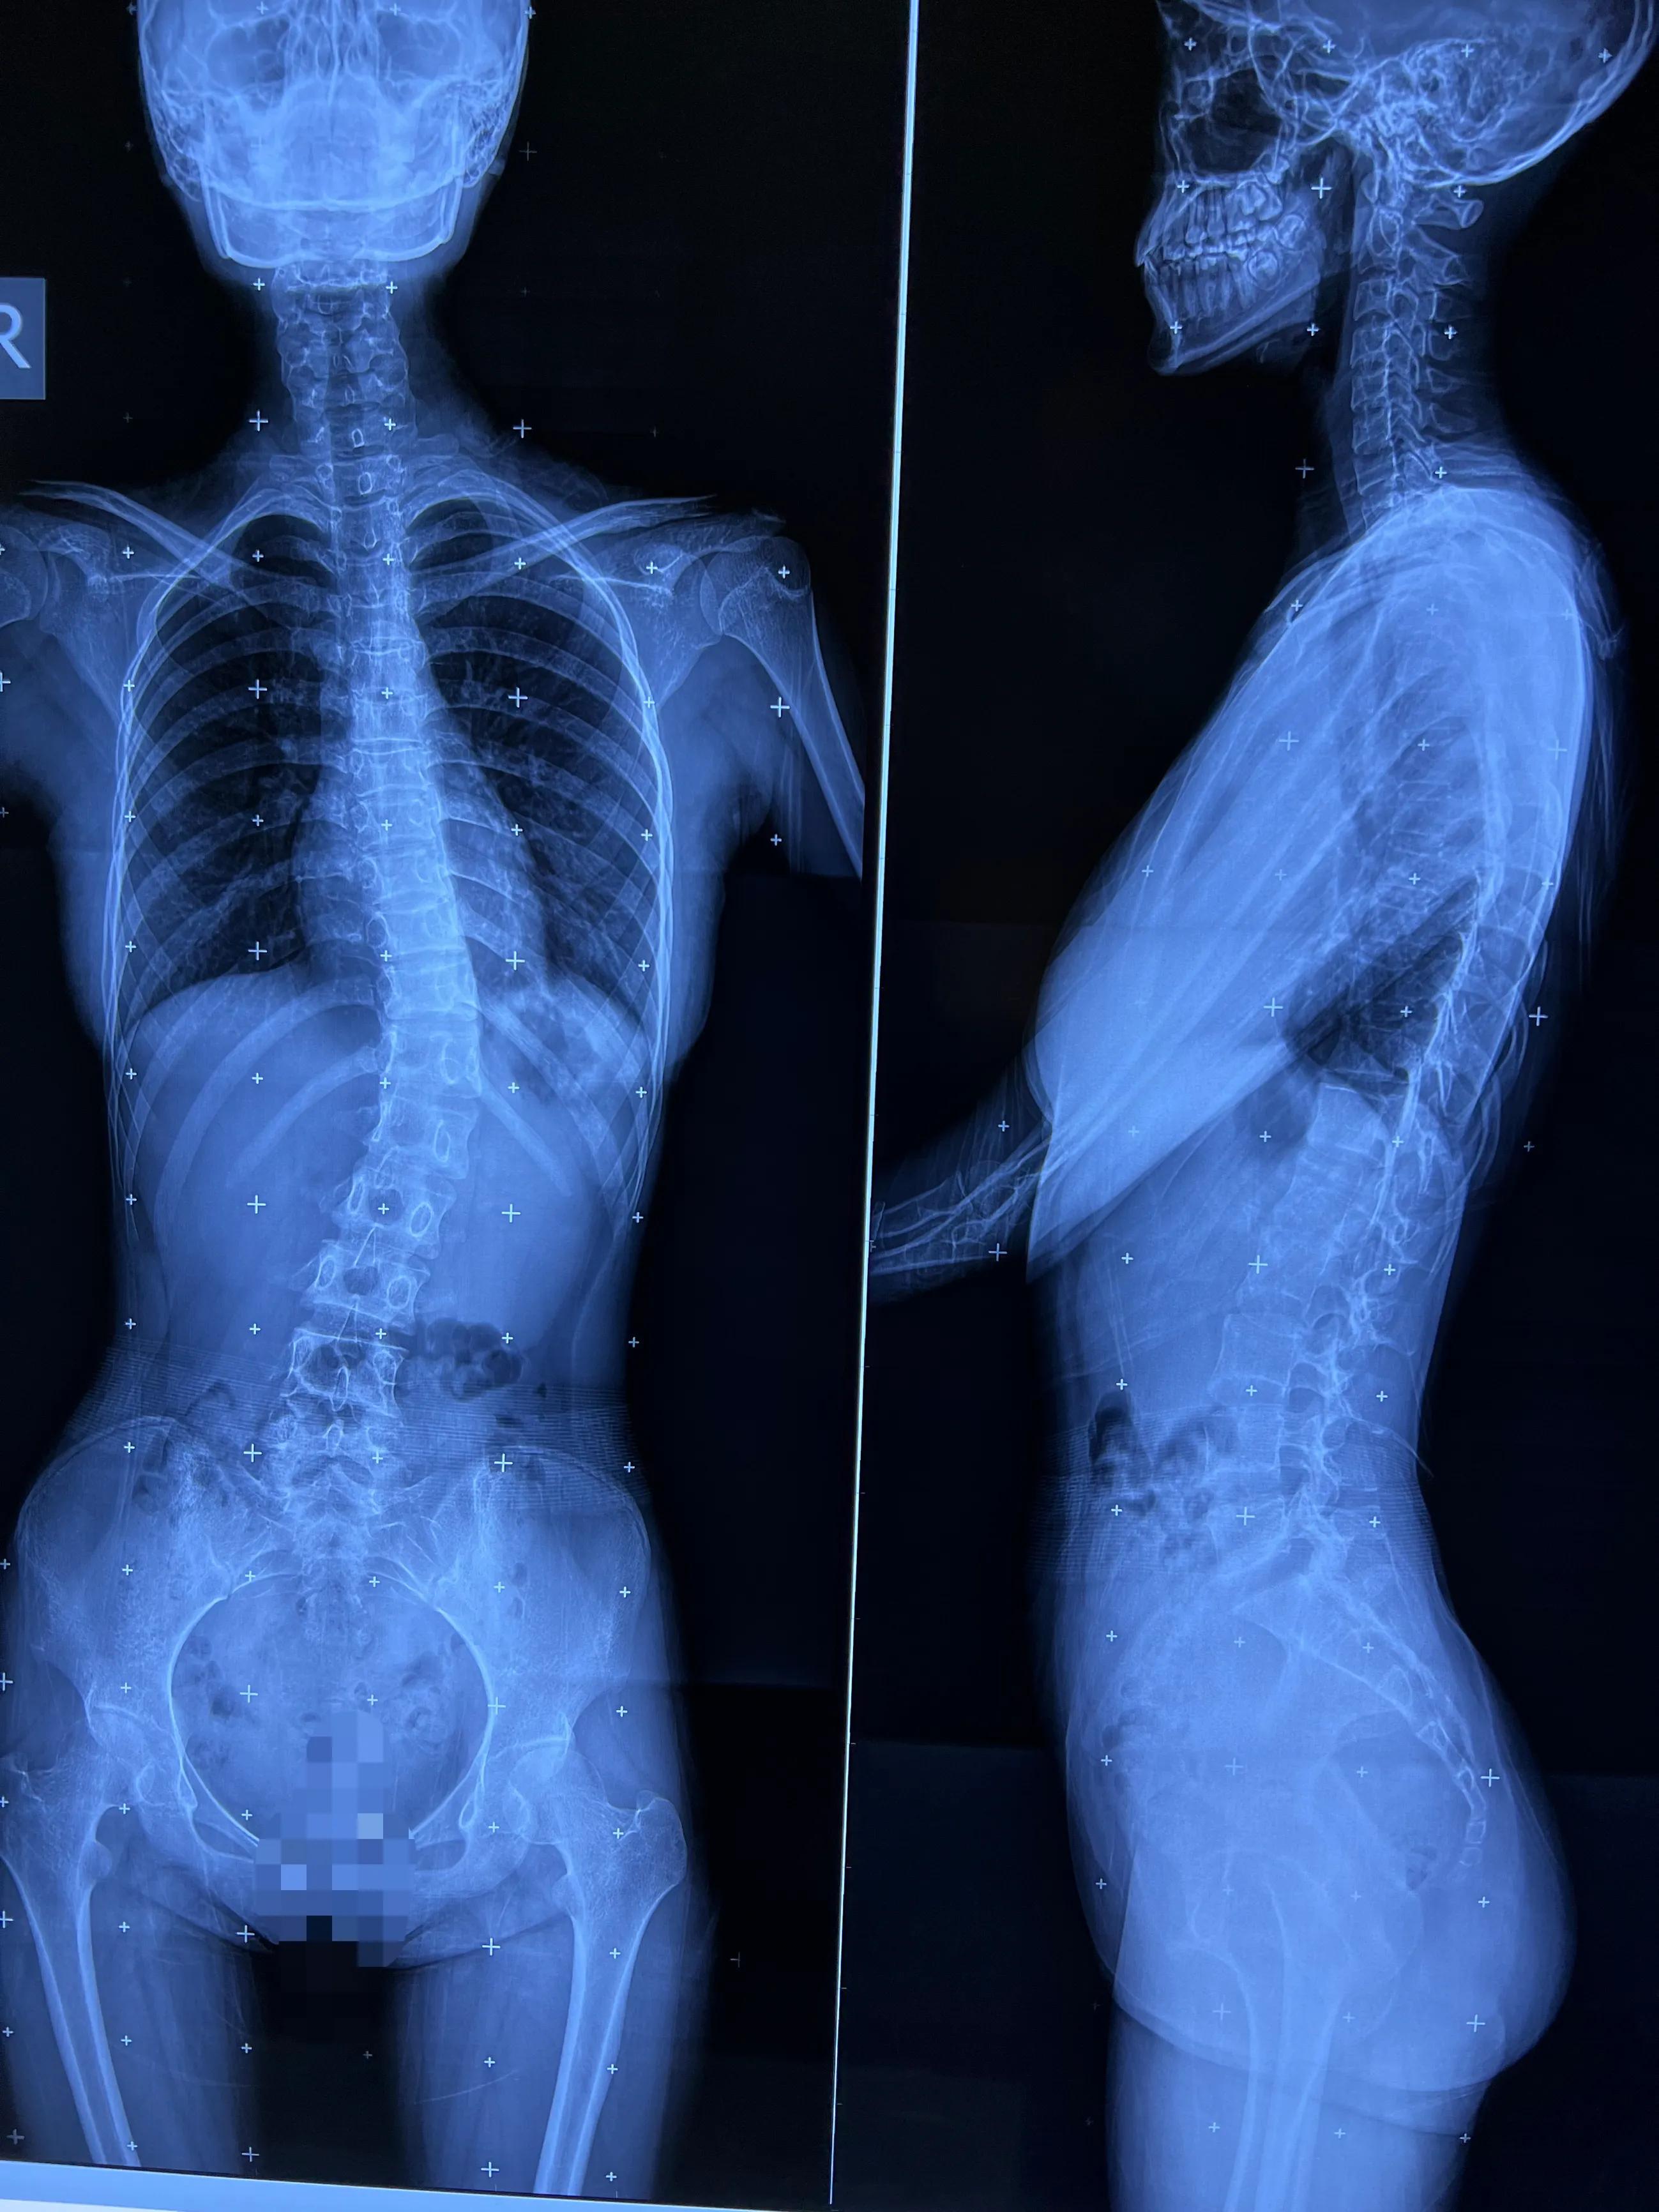

14岁女生,脊柱侧凸,家长发现高低肩后就诊

正常的脊柱,正面看从上到下,是成一直线的,从侧面看,是成“S”形的。而脊柱侧弯的青少年,他们的脊柱却偏离中线,成了拧麻花状,是一种三维的畸形。失去了平衡,脊柱的负重、减震功能也受到影响。

17岁女生,脊柱侧弯已经超过40°